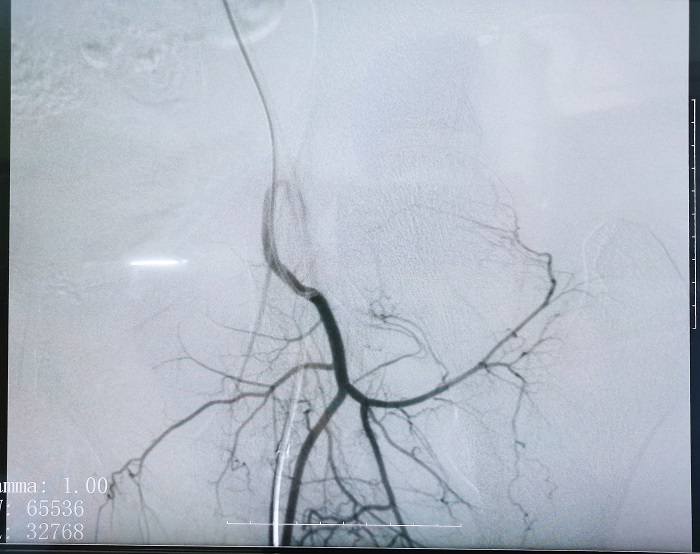

普愛平板介入中C在FTE手術(shù)過程中拍攝的造影圖像

若根據(jù)HSG的診斷,患者存在輸卵管積水,則可行輸卵管栓塞術(shù)(Fallopian tube embolization, FTE),通過介入手段,注入栓塞劑或使用彈簧圈等器材進行栓塞,可以有效地阻斷輸卵管內(nèi)的血流和組織,從而治療輸卵管積水。這個過程通常是在X線或超聲引導(dǎo)下進行的,可以清楚地看到輸卵管的情況。